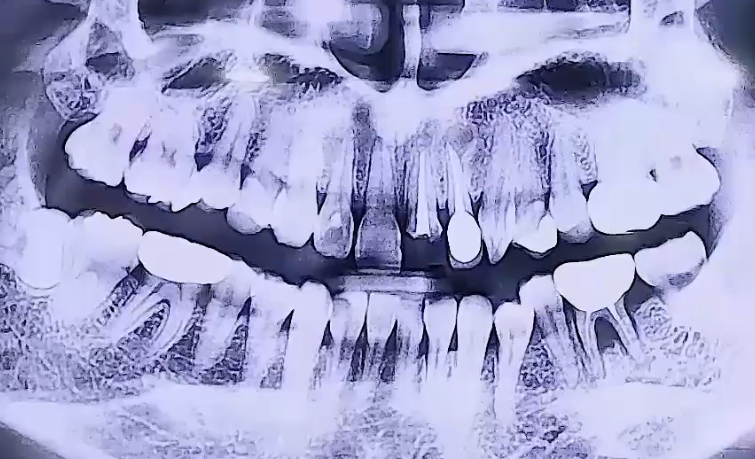

BEFORE

왼쪽 아래 어금니 통증으로 내원해주신 환자분이십니다.

왼쪽 아래 뒤에서 두번째 큰 어금니를 타 치과에서 신경치료 후

보철치료까지 마무리하신 상태였는데, 그 주변 잇몸에 염증이 생기며

굉장히 부어 오르고 통증이 심했던 것으로 확인되었습니다.

해당 치아는 겉으로는 보이지 않는 잇몸 속에 염증이 생긴 것이기 때문에

잇몸치료를 해도 치아가 안 좋아질 가능성이 크므로 발치 후 임플란트를 결정하였습니다.

또한 위 앞니는 깨져있어서 기둥을 세우고 치아를 복원하는 보철치료를 진행하였어요.

오른쪽 아래 매복사랑니가 앞쪽 치아를 향해 옆으로 누워 아주 조금 나와 있어,

그쪽에 음식물이 끼면서 염증이 생길 수 있기 때문에 발치를 해드렸습니다.